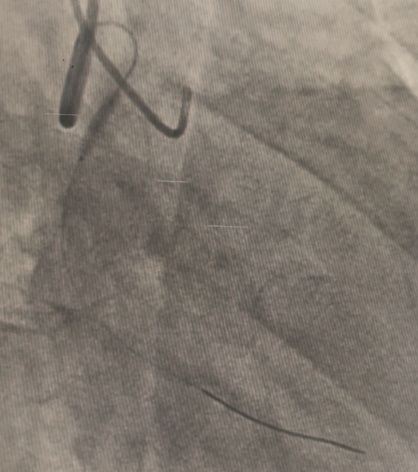

A dual access strategy was used: right radial for RCA and right femoral for LCA. For LCx CTO PCI, a Finecross microcatheter (Terumo, Japan) was advanced to the distal LCx. Predilation was done using a 2.5 ¡¿ 15 mm Firefighter balloon (Medtronic, USA) at 8 atm, followed by stenting with a 3.5 ¡¿ 30 mm Orsiro Mission drug-eluting stent (Biotronik, Germany) at 16 atm. Postdilation was performed with a 3.0 ¡¿ 15 mm Accuforce non-compliant (NC) balloon (Terumo, Japan) at 14 atm.For LAD CTO PCI, Finecross with Fielder wire (Asahi, Japan) failed to cross; Gaia First (Asahi, Japan) successfully reached the distal LAD. Predilation was performed using NC Sapphire 24 (OrbusNeich, Hong Kong) 3.5 ¡¿ 12 mm and Wedge NC (Boston Scientific, USA) 3.0 ¡¿ 15 mm. A 3.0 ¡¿ 40 mm Biofreedom Ultra stent (Biosensors, Singapore) was deployed at 14 atm. Proximal dissection into LM was noted, requiring LM–LAD stenting with 3.5 ¡¿ 22 mm Orsiro Mission and proximal optimization technique (POT) using 4.5 ¡¿ 18 mm NC Emerge balloon (Boston Scientific, USA). Intravascular ultrasound (IVUS) revealed ostial–proximal LCx disease, confirming a bifurcation lesion. Ostial LCx was predilated with a 3.5 ¡¿ 12 mm NC Sapphire balloon and stented with a 3.5 ¡¿ 14 mm Biofreedom Ultra. Final kissing balloon inflation was done with NC Sapphire 3.5 ¡¿ 12 mm (LAD) and 3.5 ¡¿ 14 mm (LCx), followed by final POT with NC Emerge 4.5 ¡¿ 8 mm balloon at 18 atm. Final shot revealed TIMI 3 flow with no dissection or perforation.